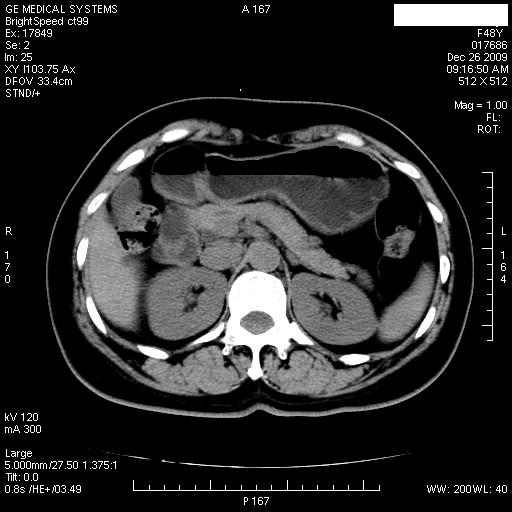

患者女性 48岁 突发上腹部疼痛,无其他不适,查体莫菲氏征阴性,ct示:胆囊炎,胆总管上端轻度扩张

图片如下:

1.图像看上去不是同一人(前组图像十二指肠未见明显异常,后组图像可见十二指肠占位)

2.后组图象印像

a.十二指肠球部前壁占位

b.坏蛆性胆囊炎,胆囊-结肠瘘(瘘口微小且时间较短,结肠内容返流入胆囊,形成胆囊壁钙化,胆囊内钙盐等沉积)

c.胆管炎,肝外胆管轻度扩张